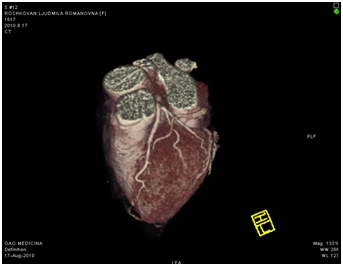

МСКТ коронарных артерий от 08.2010

Ствол ЛКА широкий, имеет ровные контуры, не стенозирован. ПНА в проксимальном сегмента имеет неровные контуры за счет кальцинированных и частично кальцинированных бляшек, просвет артерии на этом уровне сужен до 30-50%, в среднем сегменте определяется ряд пристеночных и циркулярных мягких бляшек, со стенозом артерии до 60-75%, дистальные отделы артерии малого калибра, плохо заполняются контрастным веществом. ОА нормального диаметра, заполняется контрастным веществом без признаков гемодинамически значимого стеноза. ПКА нормального диаметра, в проксимальном сегменте имеются смешанные частично кальцинированные бляшки, стенозирующие просвет до 30%, в среднем сегменте визуализируется пристеночная смешанная бляшка, стенозирующая просвет до 50-70%, дистальный сегмент не изменен. Правый тип коронарного кровоснабжения.

Трехмерная реконструкция